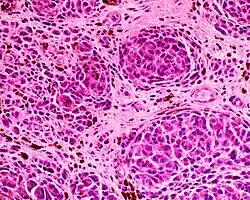

Epithelioid blue nevus

Epithelioid blue nevus -

Malignant blue nevus

Malignant blue nevus